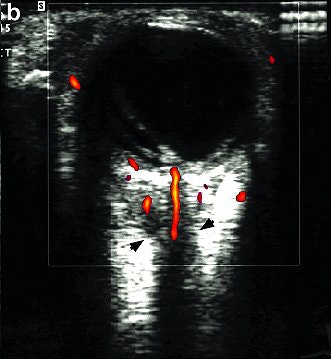

![]() |

| Color Doppler ultrasound shows that despite encasement of the optic nerve by tumor, the blood flow is intact to the posterior eyeball through branches of the short posterior ciliary arteries and the central retinal artery. Images courtesy of Dr. Deepak Bedi. |

"Color Doppler and A-mode ultrasound are invaluable for characterizing masses," they pointed out. "The ultrasound exam is rapid, cost-effective, has no contraindications, such as pacemakers in MRI. It avoids the irradiation associated with CT and the need for sedation in children."